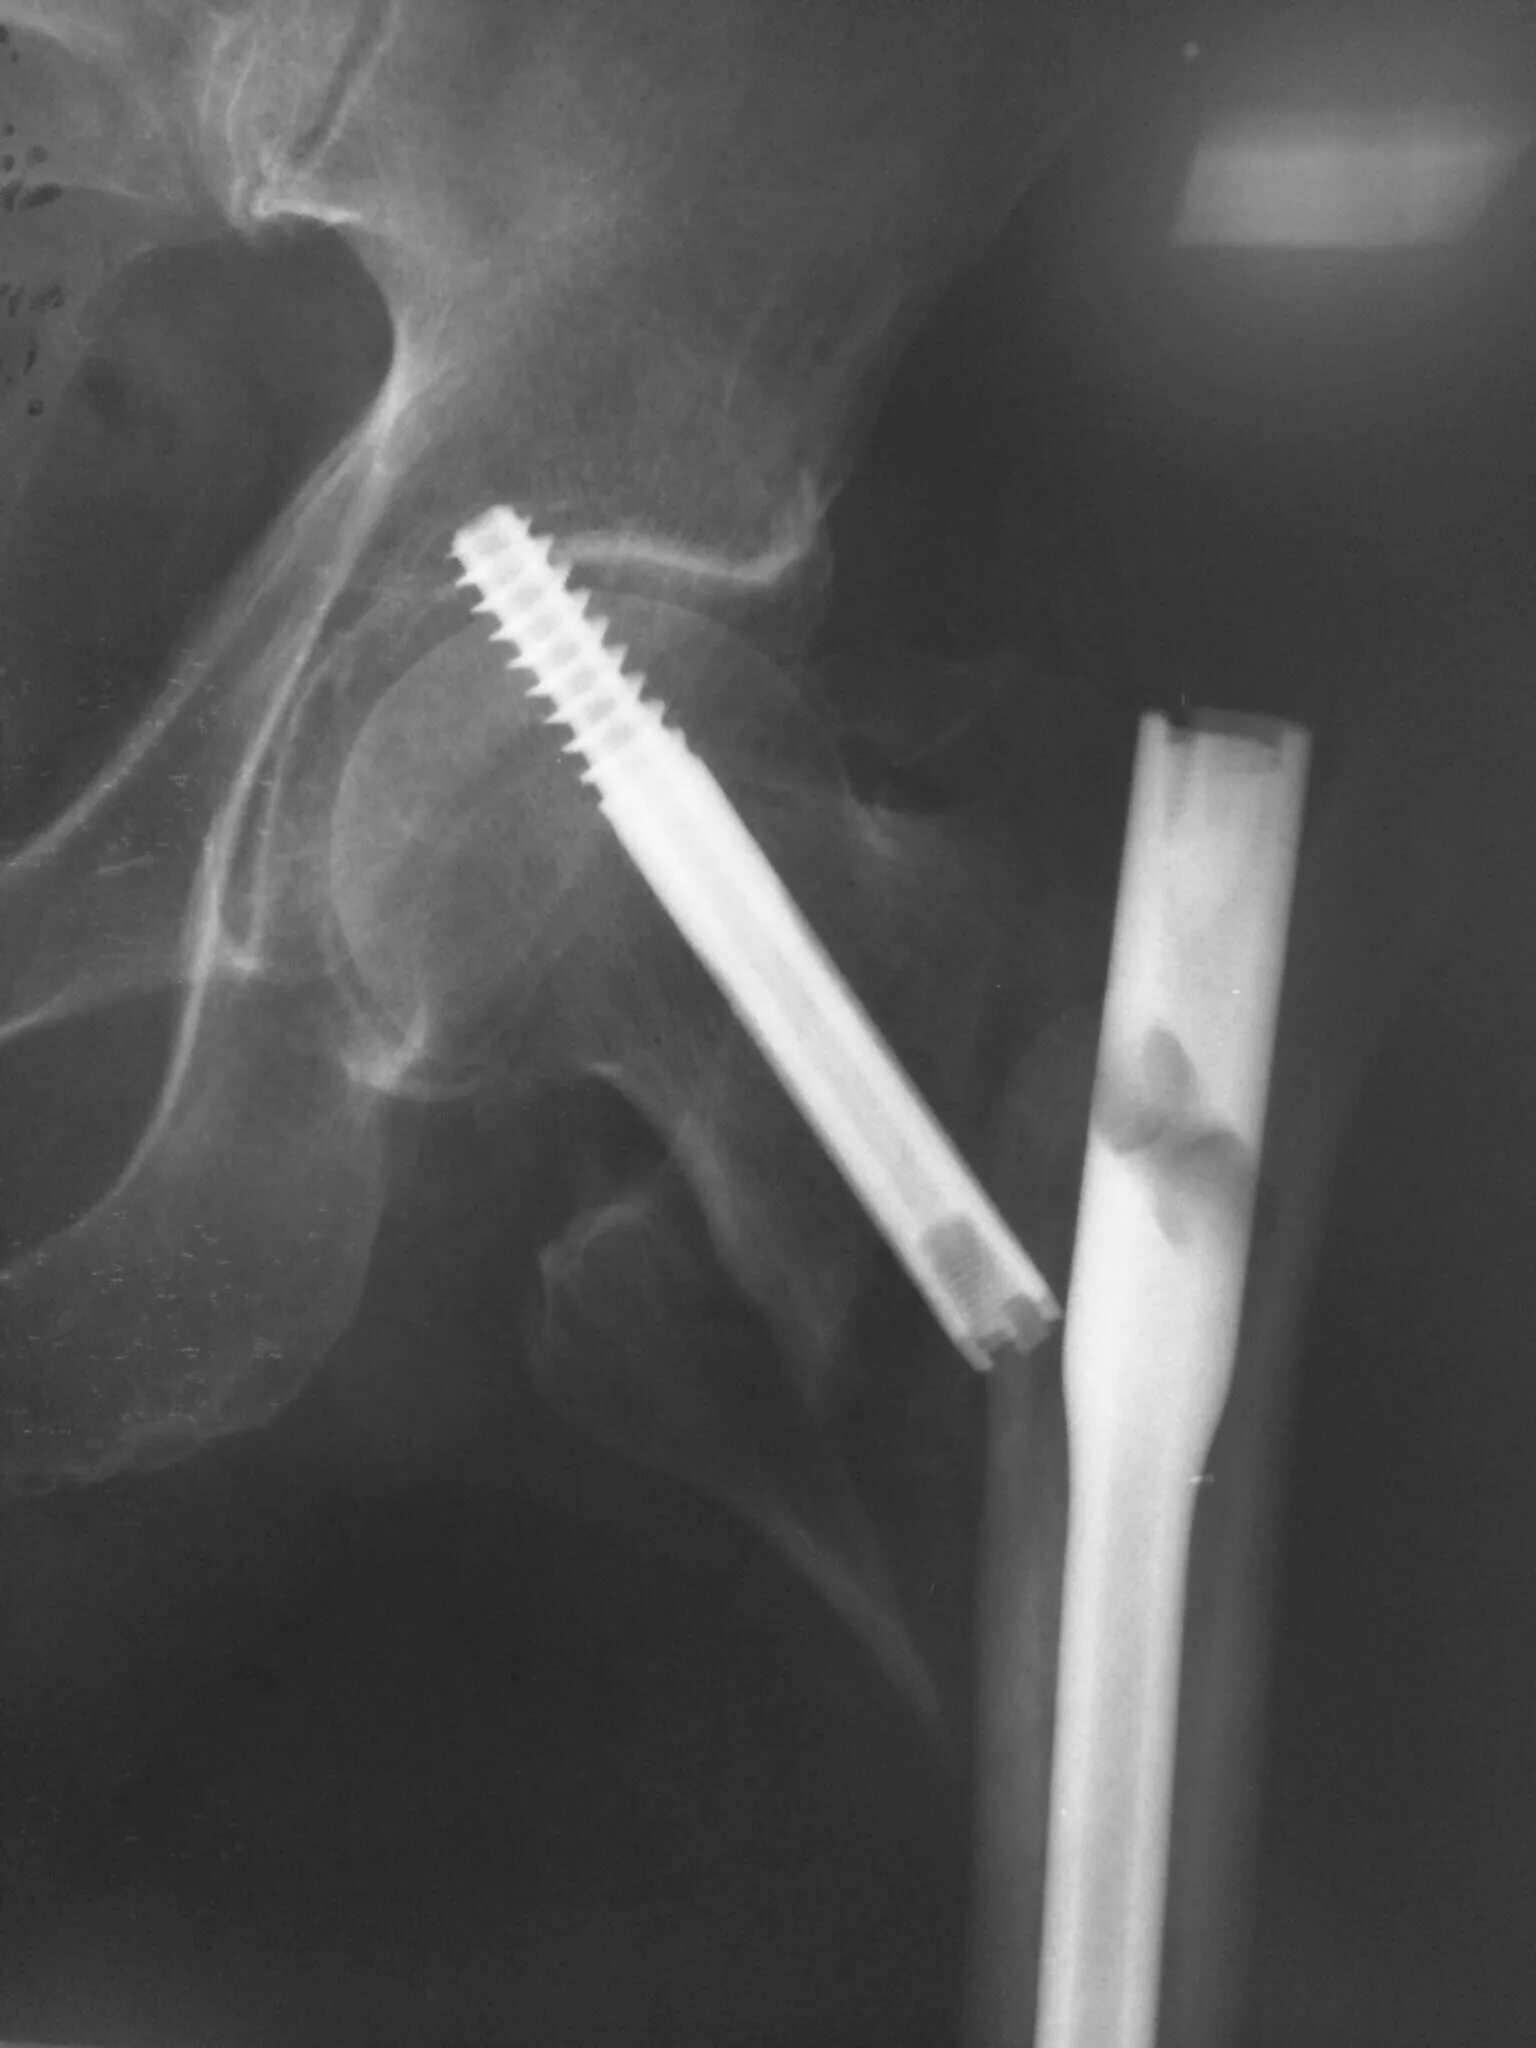

Патологический перелом бедра